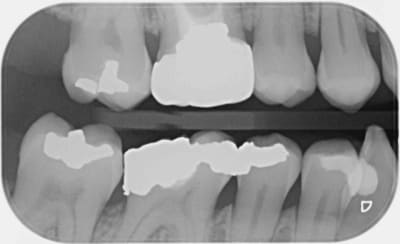

Ce message n'apporte rien au débat, c'est juste pour parler de cette patiente qui n'avait pas donné suite au devis pour couronner la 46. Au contrôle annuel suivant, la dent était couronnée, tout allait bien. Il a fallu que je lui pose la question pour qu'elle m'explique, sans la moindre gêne, que sa mutuelle GROUPAMA l'avait orientée vers un dentiste partenaire "moins cher".

Rien que sur la radio, je vous laisse admirer la qualité de la morphologie occlusale, le profil d'émergence, les points de contact (ou leur absence)... Je n'ai pas osé prendre de photo de ce blockhaus.

Bref, un an après, voici que la patiente revient pour me dire que la couronne ne va pas du tout, que ça la gêne.

Je me suis donc fait un malin plaisir de la renvoyer vers ce con-frère,

ET CA FAIT DU BIENNNNNNNNNNNNNN.